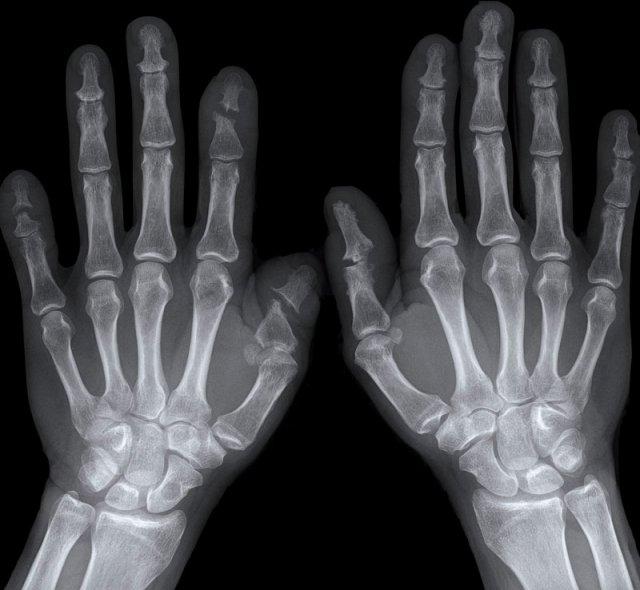

Hình ảnh bào mòn xương vùng rìa điển hình và hẹp khe khớp tại các khớp MCP 3-5.

Lưu ý hình ảnh hẹp khe khớp đồng đều tại các khớp MCP.

Các khớp liên đốt gần (PIP) chỉ biểu hiện hẹp khe khớp tối thiểu.

Đây là trường hợp viêm khớp dạng thấp giai đoạn cuối với các thay đổi bào mòn nặng nề và đứt dây chằng gây trật khớp tại các khớp MCP.

Phân ly xương thuyền – xương nguyệt (mũi tên trắng) là dấu hiệu thường gặp do tình trạng viêm lan tỏa khối xương cổ tay. Cả tình trạng phân ly lẫn viêm đều có thể gây hẹp khe khớp quay – cổ tay.

Lưu ý hình ảnh bào mòn xương đầu dưới xương trụ kèm theo sưng nề phần mềm xung quanh (mũi tên xanh).